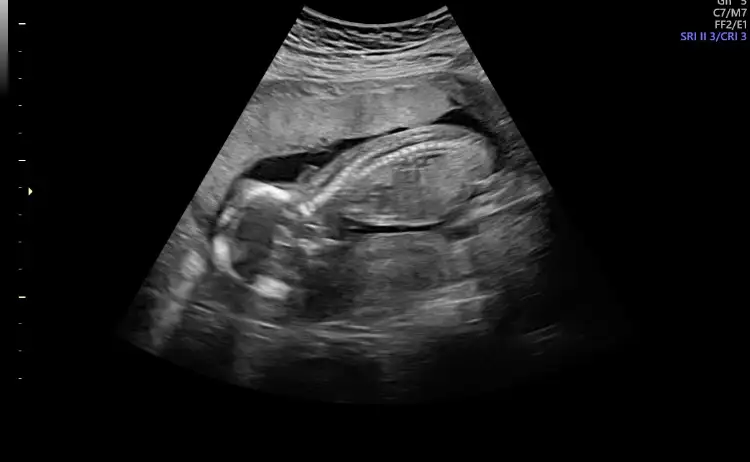

Cnm ayna gibi usg hep yüsütüydü asla kıpırdamadı neden dedim uyuyor dedi banada hiç bilgi vermez vermedi direk kız dedi kesin mi dedim kesin dedi, sinir oldum insan bir uyandırır zorlar falan 10dk bakmadı ama fotoda kız gibi yinede 20yi bekliyorum düzgün göreyim anlatsın bi doktorda ya bak fotolarıma, şu son fotoda bacak arası gözüküyor ama emin olamıyorum çünkü göstermedi doktor şurası şu diyeYüz üstü olduğunu nerden anlıyorsun canım. Ben hiçbirşey anlamıyorum ya. Doktor da demiyor şu pozisyonda becak arası şu organ var eli şu kolu şu. Son gittiğimdeki doktor söyledi sadece o da 2 dakika baktı bakmadı kalktım.

Hngisiymiş pipiKizlar beni bile tereddutte biraktirdiniz cinsiyet konusunda aksam aksam ultrasyon resmine baktimdegisirmi bilemiyorum artik ayrintiliya daha var doktor pipisi bu dedi sag tarafa bakin

Kiz kafasi obur taraftabu alt bolumu bacak arasiymis orasi degisirmi dedim bak simdi burda gorunen degisirmi dedi. Bilemedim artik